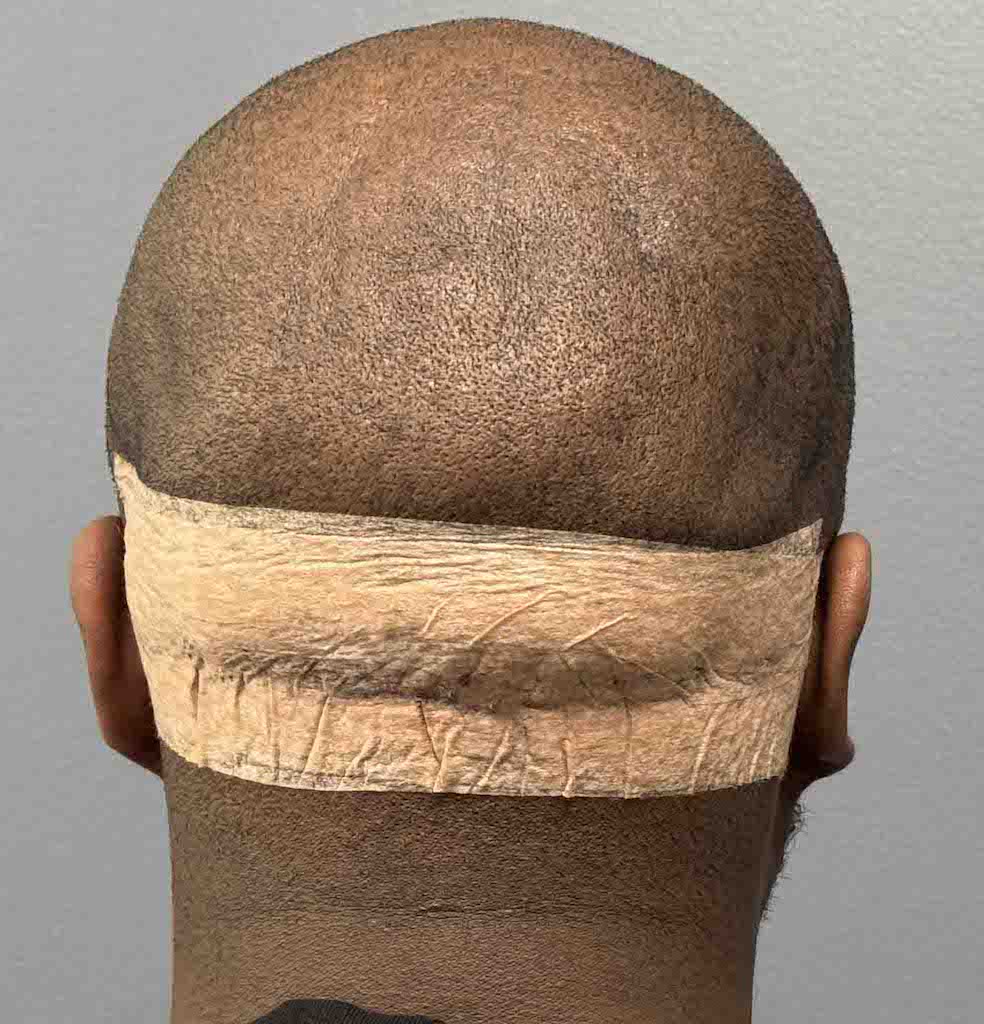

Patient 129

Desire for reduced width/convexity on the sides of his head.

Head narrowing using a temporal muscle transposition technique seen one day postop. He also had an concurrent occipital skull reduction done hence the tape over his incision.

Desire for reduced width/convexity on the sides of his head.

Head narrowing using a temporal muscle transposition technique seen one day postop. He also had an concurrent occipital skull reduction done hence the tape over his incision.